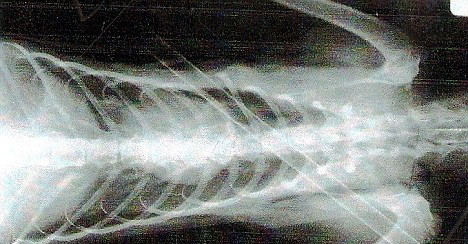

Si-a pierdut cu siguranta una dintre cele noua vieti! Dave se juca undeva in apropierea casei, atunci cand a fost strapuns de o sageata de aproape 36 de centimetri.

Veterinarul care l-a tratat pe motanul de 11 luni a spus ca acesta a avut mare noroc: pentru ca sageata nu avea un varf ascutit, majoritatea organelor vitate si a arterelor principale au fost pur si simplu impinse si nu strapunse.